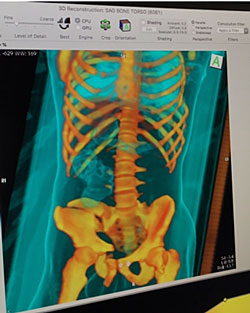

Exhibit 2. Three-Dimensional Scan and CT Scan

Three-Dimensional Scan and CT Scan

Source: Photos taken by Danielle McLeod-Henning (NIJ) at the University of New Mexico (2016).

The first image shows a three-dimensional rendering of a torso showing hip fractures. The second image is a computed tomography (CT) scan of a torso on a coronal plane. Both images were viewed through a program called OsiriX.